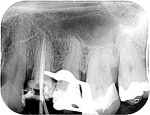

Molar retreatment